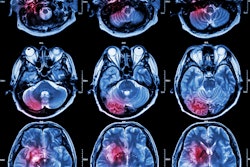

Although ischemic stroke is fairly rare as a cause of dizziness in the ED setting, it can be difficult to discern whether dizziness is caused by nonischemic factors -- a problem that presents a "diagnostic dilemma" for ED clinicians, Tegtmeyer and colleagues noted.

"This dilemma is further hindered by the poor sensitivity of CT and CTA for posterior fossa strokes," they wrote.

Previous research has suggested that MRI offers high sensitivity for detecting posterior fossa strokes, although conventional MRI may not be readily available in all practice settings, the group explained. That's why other imaging strategies such as portable MRI and CT perfusion could help, especially since they may have higher sensitivity than CT/CTA.